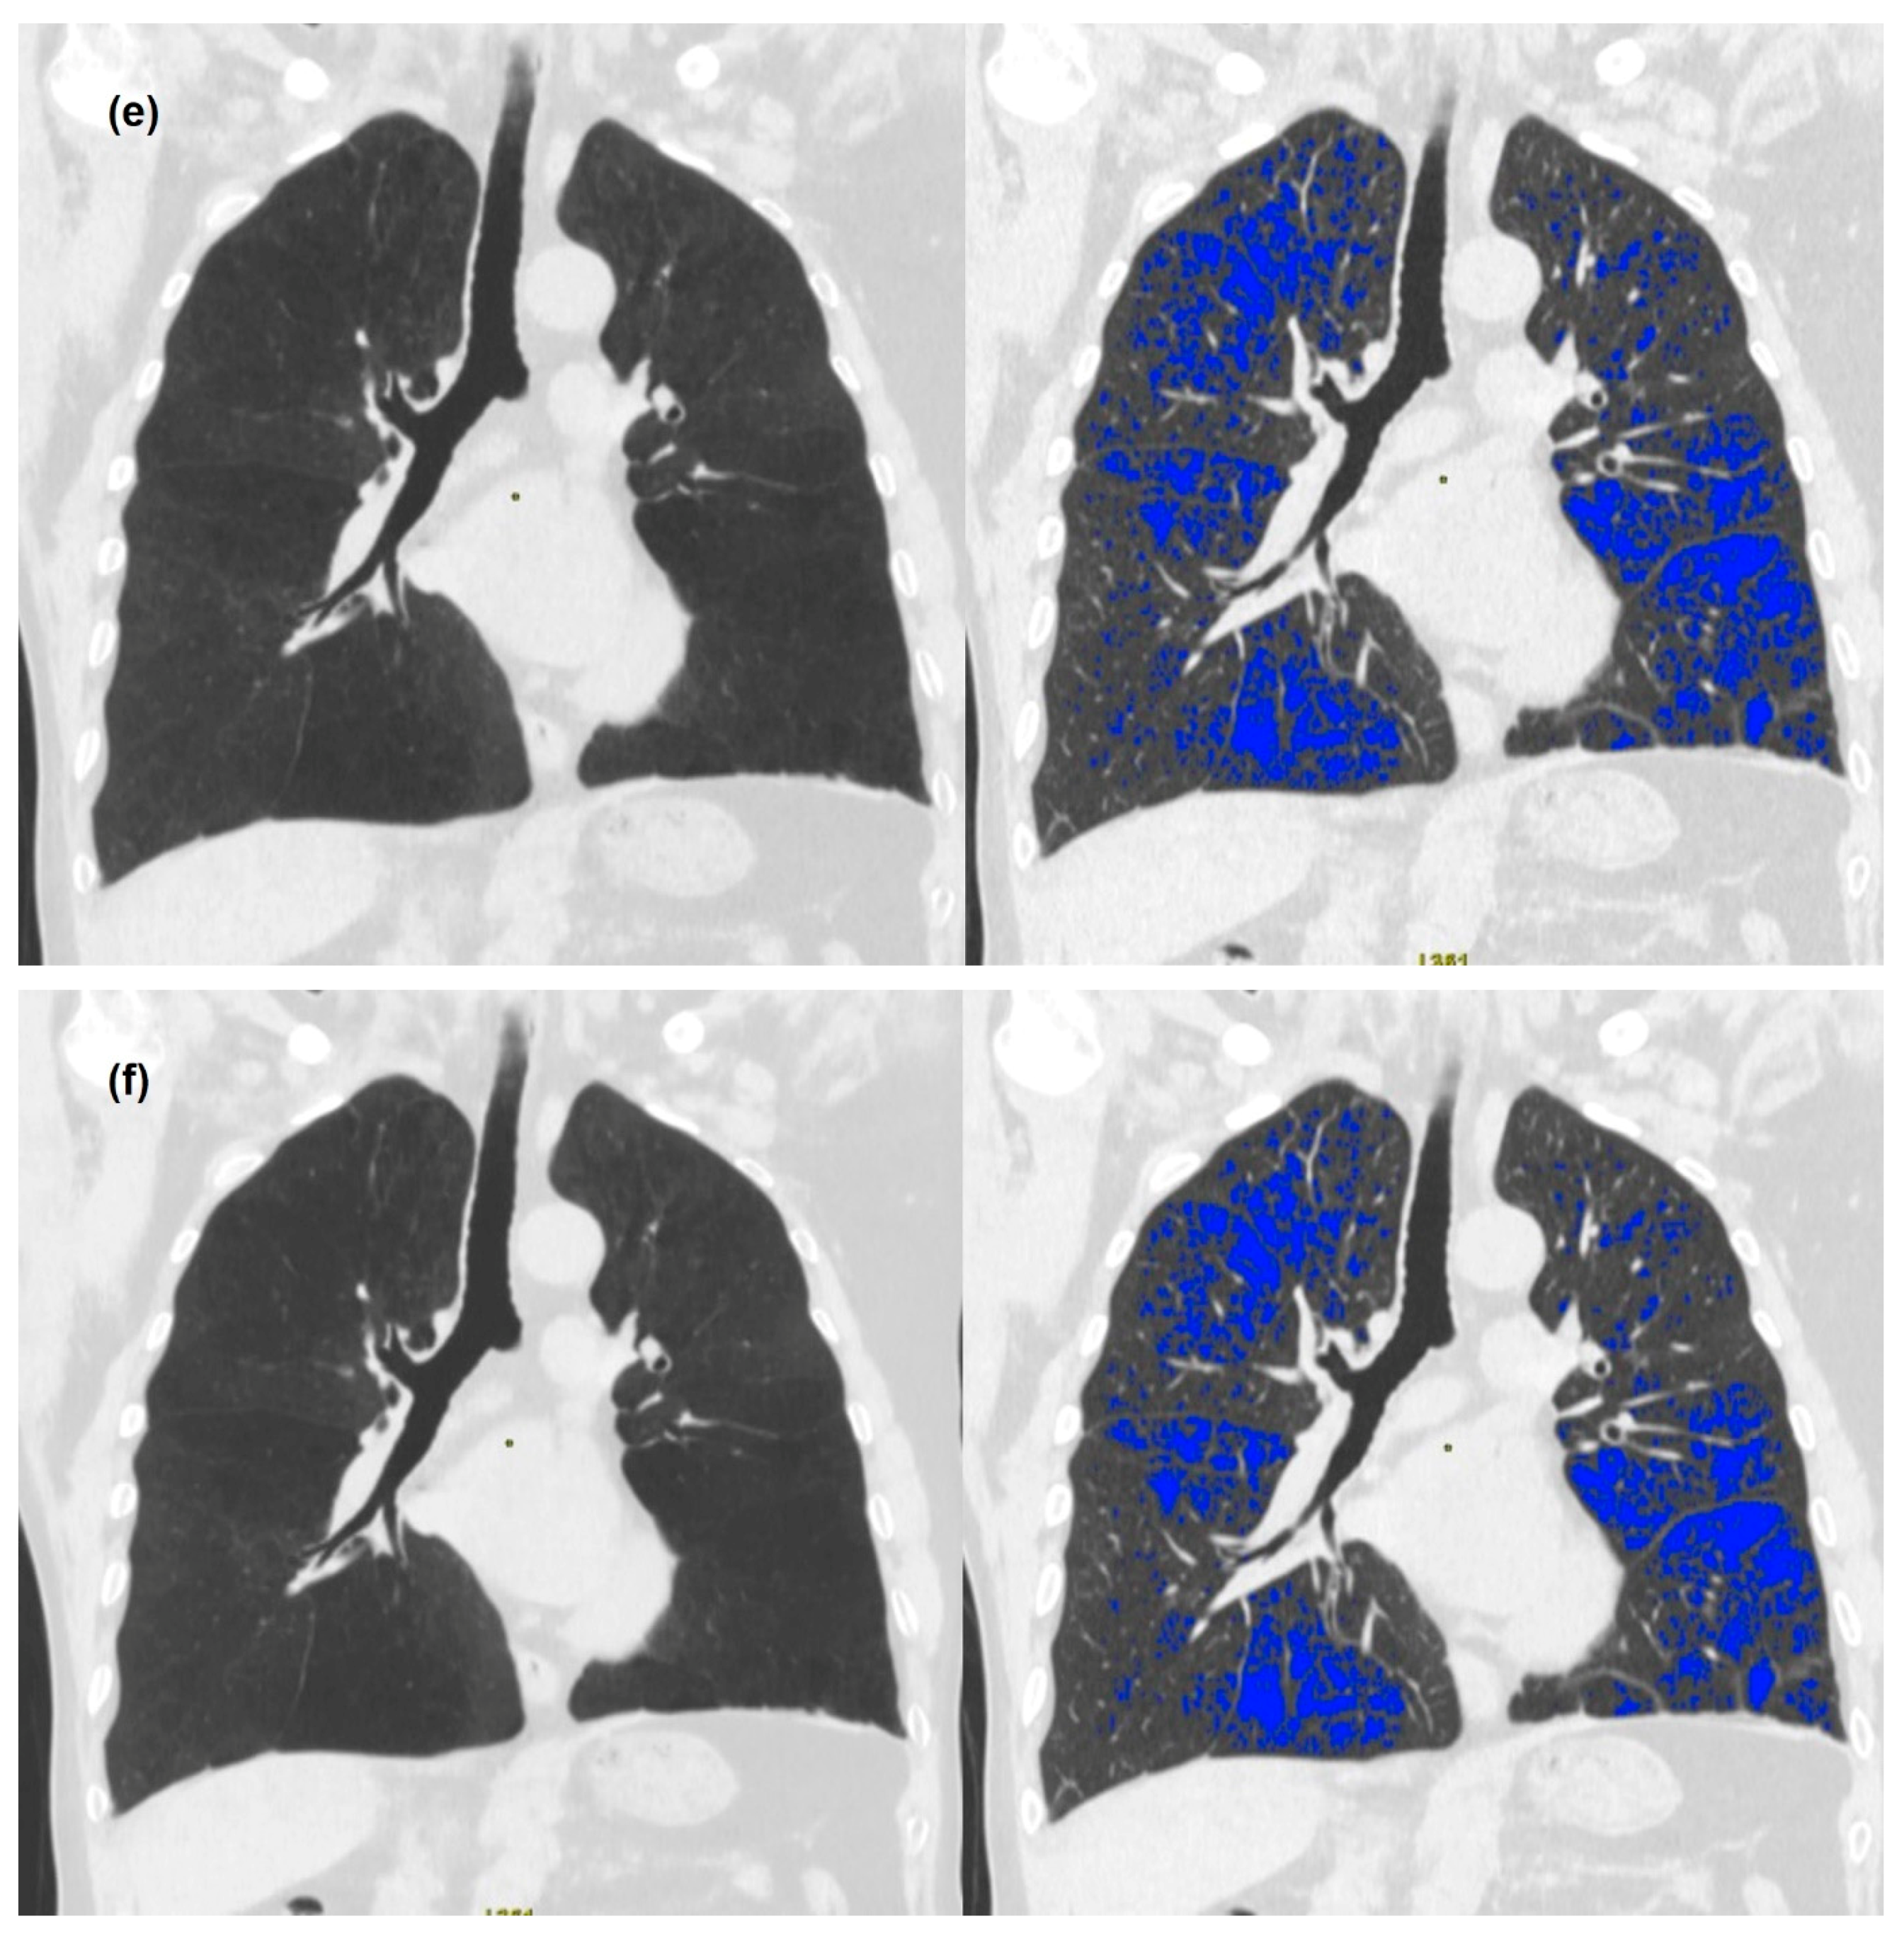

3.2. Quantitative Measurements of Standard-Dose and Ultra-Low-Dose CT